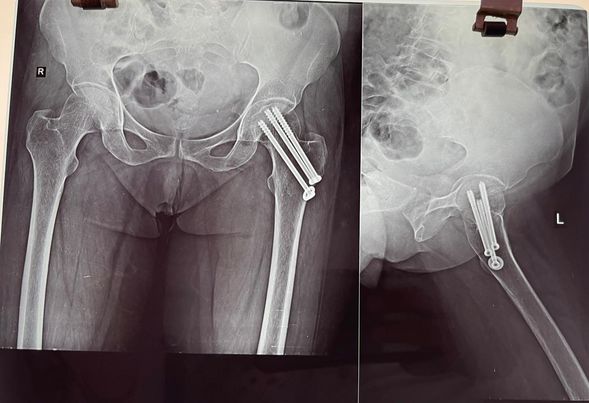

Most neck of femur fractures are treated with partial or total jointreplacement surgeries. however doing so limits active lifestyle in younger individuals. Especially in the Indian system of living. that is why it’s important to take such fractures as surgical emergencies in young people like this 43 year old woman and treat them with screw fixation preferably withing 6 hours of the injury.

This particular patient’s fracture has healed completely and her movements are normal and painless at 7th month, she can now offer Namaz according to her custom. Something that is impossible after a total or partial hipreplacement.